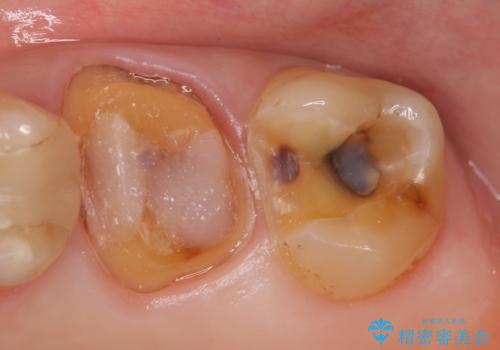

- 左上6番目の歯が欠けてしまったので診て欲しいといらっしゃった方の症例です。

左上6番目は銀歯・虫歯を除去後、オールセラミッククラウンにて補綴を行いました。

左上7番目も虫歯だったため、銀歯・虫歯を除去後、セラミックインレーにて修復を行いました。